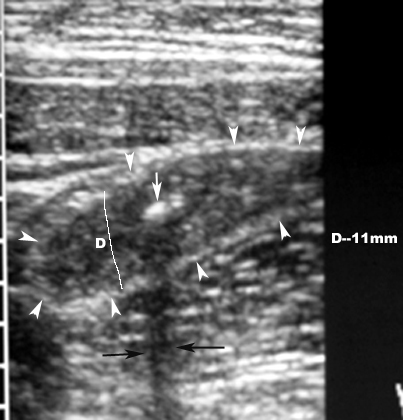

What are the radiological findings of appendicitis in abdomen ultrasound?

- The most sensitive sign of appendicitis from ultrasound is a non compressible appendix with a diameter of 7mm or greater.

- Other findings may include:

- appendicolith

- thickened appendiceal wall

- abscess

- fluid around the appendix

Appendicitis with Appendicolith

Findings:

- White arrow points to appendicolith.

- D is the diameter of the appendix measuring more than 7 mm.

- Arrowheads point to distended appendix.

- Black arrows point to posterior shadowing.